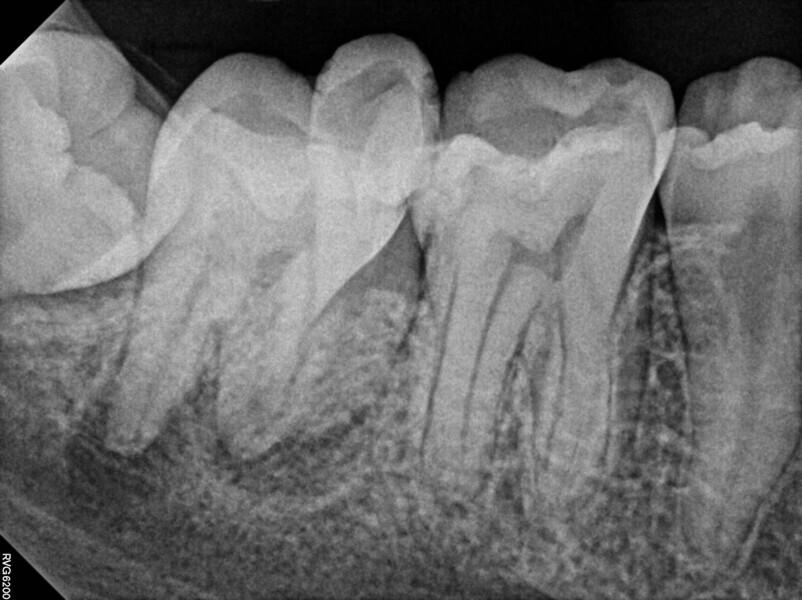

Fig. 14a: Case treated with Bassi Logic controlled memory nickel titanium files. Note the visualization of the third root on this lower molar and conservative canal preparation shape. (Courtesy of Dr. Alex Chan)

Fig. 14b: Case treated with Bassi Logic controlled memory nickel titanium files. Note the visualization of the third root on this lower molar and conservative canal preparation shape. (Courtesy of Dr. Alex Chan)